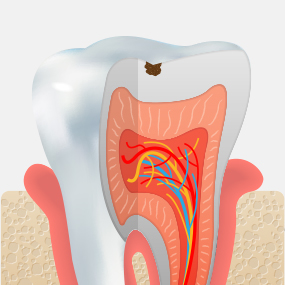

충치는 흔한 질환이지만 스스로 회복되지 않습니다. 통증이 있어도 치료를 미루다 보면 적절한 시기를 놓쳐 더 많은 비용과 시간이 들 수 있습니다. 정기적인 구강검진으로 문제를 조기에 발견하고 신속히 치료받는 것이 건강을 지키는 가장 현명한 방법입니다.

단계별 충치치료를 통해

최선의 진료를 찾고

자연치아를 최대한 보존합니다.

법랑질 충치

치아 겉면인

법랑질의 충치로 통증이 거의 없습니다.레진치료

상아질 충치

법랑질 안쪽에 있는 상아질까지 충치가 진행되어 뜨겁거나 차가운 음식을 먹으면 시린 증상이 나타납니다.

인레이

치수염 충치

상아질 안쪽 신경까지 염증이 진행되어 극심한 통증으로 참기 어려운

정도가 됩니다.신경치료 + 크라운

치주 괴사

치아 내부에 있는 조직이 괴사되고, 뿌리 주변의

염증으로 인하여 뼈가 점차 소실됩니다.발치 + 임플란트